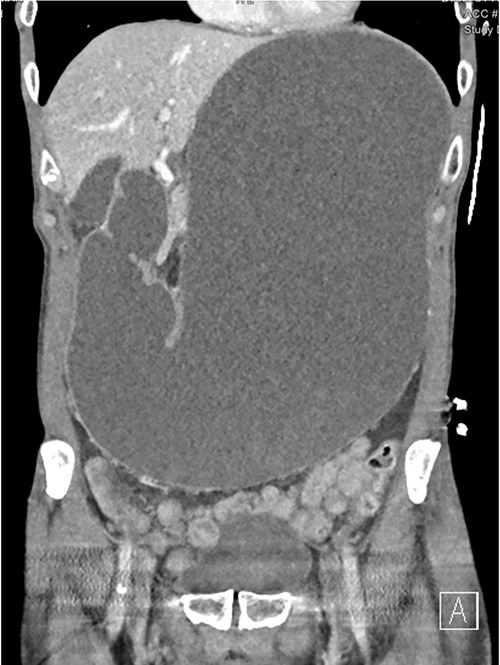

A 73-year-old male was transferred from a private hospital to the local public hospital 5 days post left total hip replacement with a 2-day history of nausea, bilious vomiting and colicky abdominal pain. His bowels had not opened since prior to the procedure. His background included previous right total hip replacement, benign prostate hyperplasia and depression. His medications included mirtazapine, tamsulosin, calcium carbonate and denosumab. He is a non-smoker and does not drink alcohol. On examination his observations were all within normal limits and he appeared to be very slim build. His height was 174 cm and he weighed 49 kg with a body mass index of 16.2. His abdomen was generally tender and distended, but not peritonitic. His blood results showed a serum potassium of 3.2 mmol/L, sodium 148 mmol/L, magnesium 0.94 mmol/L, albumin 34 g/L, creatinine 104 μmol/L, eGFR 61 ml/min (acute kidney injury), white cell count 7.7 × 109/L, haemoglobin 114 g/L. A computed tomography (CT) scan of his abdomen (Figs 1–3) showed a grossly distended stomach measuring 26.2 cm × 14.3 cm × 14.6 cm. It appeared fluid filled with moderate distension of the first and second part of the duodenum. The third part of the duodenum was partly fluid filled with an abrupt luminal collapse within the distal aspect where it passes between the superior mesenteric artery and aorta. The aorta mesenteric angle was reduced to ~23°. The remaining small bowel was decompressed with no free fluid or gas.

CT showing grossly distended stomach, first and second part of duodenum with sudden collapse and obstruction of duodenum (green arrow) at the superior mesenteric artery (blue arrow).